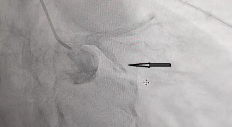

独立完成“冠脉血管球囊扩张+冠状动脉溶栓术”,成功挽救患者生命,进一步提高了急性胸痛患者的救治成功率。

溶栓前

溶栓后

冠脉造影及介入治疗,使越来越多冠心病患者从中受益,少跑路,少花钱,治好病。